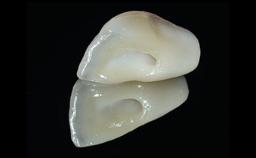

Replacement of a Missing Upper Left Central Incisor: Late Placement of an RC Bone Level Implant, CAD/CAM Zirconia Abutment

A healthy 37-year-old female patient was referred for a consultation on the replacement of missing tooth 21 with an implant-supported restoration. She stated that several years previously the tooth had been traumatically avulsed following a motor vehicle accident. The tooth was replaced with a three-unit fixed partial denture (FPD) immediately afterwards. Over time, she became disillusioned with the FPD and looked for a different option, including orthodontic therapy. She presented still in her orthodontic appliances, with the pontic sectioned free from the FPD but attached to the archwire. Her orthodontist felt that orthodontic treatment had been successfully completed, but nevertheless referred her before removing the appliances in case adjustments were necessary.